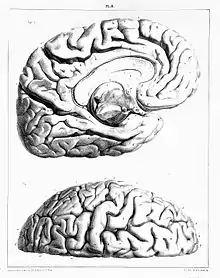

In 1844 Foville published Traité complet de l'anatomie, de la physiologie et de la pathologie du système nerveux cérébro-spinal on the anatomy of the nervous system of the spinal cord, regarded as one of the best works on the subject prior to the invention of the microscope.[2]